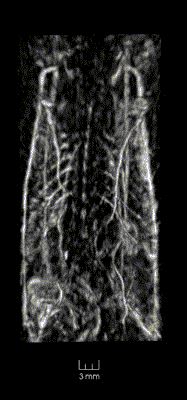

Image 2D Projections: Mouse Injected with Contrast Agent

After intravenous injection of PEGylated gold nanorods as contrast agent, microvasculature as small as 50 micron in soft tissue and even bones (ribs and spine) was visualized even though the system spatial resolution is only 500 micron. Redistribution kinetics of gold nanorods (GNR) was observed in tissue showing presence of GNR in the vasculature shortly after injection, then gradual transfer of the contrast to the organs (such as liver and spleen) serving as filters for nanoparticles.